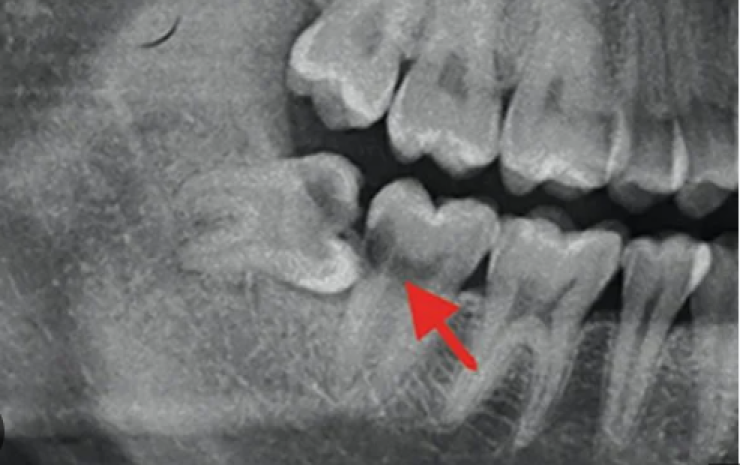

X-quang cho thấy răng khôn mọc ngầm trong xương.

Răng khôn mọc lệch, đâm vào răng số 7.

Sâu răng số 7.